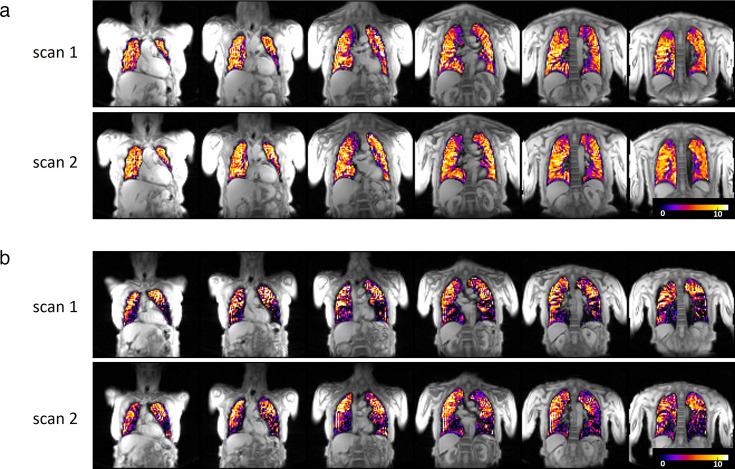

Study design and methods: 13 patients with mild-to-severe COPD and 13 HVs underwent PFTs, lung clearance index (LCI) measurement, incremental exercise test (patients only) and two lung MRI scans at 3 T. For T2*-OE-MRI, participants were fitted with a non-rebreathing face mask and given 100% oxygen during image acquisition.

Results: Patients (age: 63 (55-72) years, forced expiratory volume in 1 s (FEV1): 63 (36-79) %predicted, median (IQR)) had evidence of pulmonary gas trapping, small airway disease (SAD) and ventilation heterogeneity. During T2*-OE-MRI, the magnitude of the percentage difference between mean signal intensity at normoxia and hyperoxia (percent signal enhancement (PSE)) and the enhancing fraction (EF) were lower in patients versus HVs (2.77 (2.19-4.19) vs 5.34 (4.33-5.61) % and 0.74 (0.66-0.77) vs 0.89 (0.82-0.94), respectively, both p<0.001). Intraclass correlation coefficient values indicated moderate (0.74) and good (0.80) repeatability for PSE and EF, respectively. PSE and EF significantly correlated with FEV1, LCI and SAD indices, and in COPD, they correlated with measures of exercise capacity, dynamic hyperinflation and dyspnoea intensity during exercise.

Interpretation: In patients with COPD, T2*-OE-MRI is feasible and repeatable and provides regional information on pulmonary ventilation that is linked with physiological measures of disease severity, functional limitation and exertional dyspnoea.